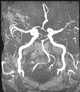

Diffuse atherosclerosis